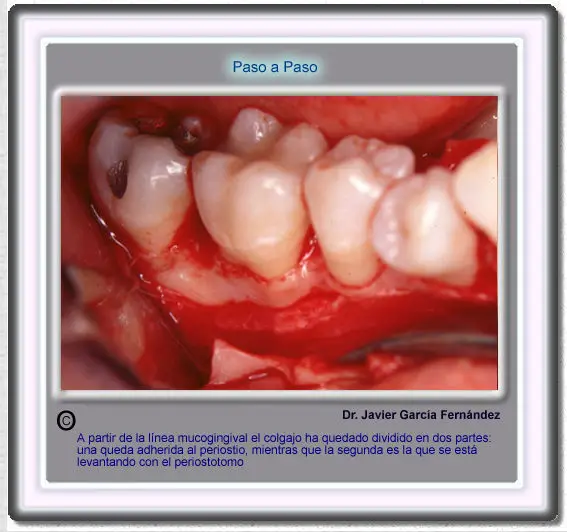

Atlas of Surgical Techniques in Periodontics. Chapter III.